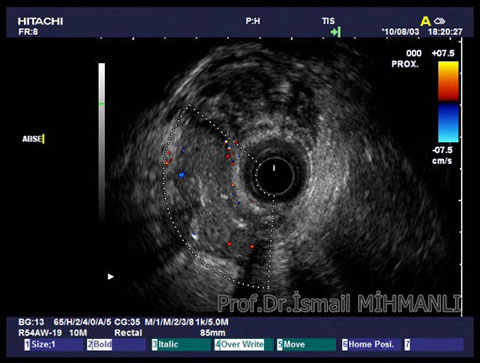

İntersfinkterik fistül

İntersfinkterik abse